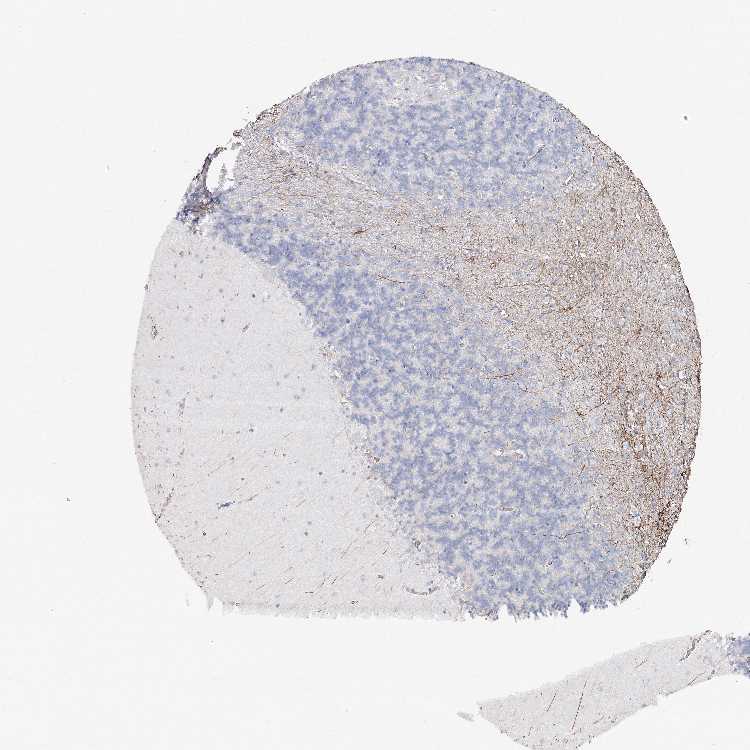

CEREBELLUM - Antibody stainingi

Antibody staining in the annotated cell types in the current human tissue is reported as not detected, low, medium, or high, based on conventional immunohistochemistry profiling in selected tissues. This score is based on the combination of the staining intensity and fraction of stained cells.

Each image is clickable and will lead to virtual microscopy that enables deeper exploration of all samples and also displays staining intensity scores, fraction scores and subcellular localization as well as patient and tissue information for each sample.

Antibody HPA034631Antibody HPA071347Antibody CAB033265Antibody CAB037325

Purkinje cells Not detectedLowMediumNot detected

Cells in granular layer MediumNot detectedNot detectedLow

Cells in molecular layer MediumNot detectedLowNot detected